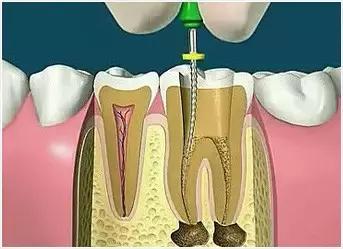

4、根管预备

根管清理成形的目的是去净根管壁上的感染物,通过根管器械的切削作用去除感染的牙本质并清理根管壁细菌以利于根管充填。

5、根管冲洗、消毒

根管冲洗的目的是清除微生物、冲掉残渣,润滑根管器械和溶解有机残渣。然后,再进行根管消毒,使根管内达到无菌状态。